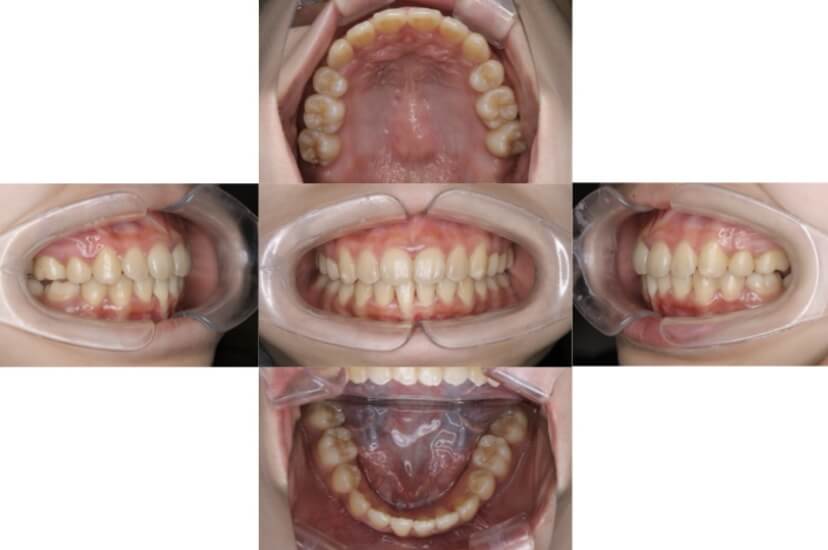

BEFORE

AFTER

上下顎叢生(上下の前歯のガタガタ)のケースです。

装置はラビアル(上下表側)で、上下顎の小臼歯を4本抜歯を行っています。抜歯したスペースを使って、上下の前歯の後方移動と叢生(ガタガタ)の改善を行っています。

主訴 八重歯を治したい。

年齢・性別 25歳 女性

お住まいの地域 神奈川県川崎市

治療方針 抜歯スペースを利用して上前歯の叢生(ガタガタ)の改善

抜歯部位 上下顎左右第一小臼歯

使用装置 ラビアル(上下表側)、顎間ゴム

治療期間 1年11か月

治療回数 16回

リテーナー クリアリテーナー